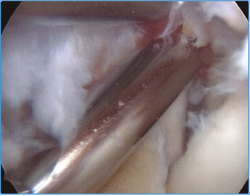

La capsulotomía anterior la iniciaremos de medial a lateral, aproximadamente un centímetro proximal a la punta de la coronoides, utilizando un vaporizador "de gancho" (instrumento que nos parece muy útil para esta tarea, ya que nos permite controlar muy bien la profundidad de la resección de la cápsula para evitar lesionar estructuras neurovasculares próximas); también utilizamos la pinza Basket para resecar la cápsula, sobre todo en los casos en los que está muy engrosada y endurecida (Figura 7). Para disminuir el riesgo de lesión del nervio interóseo posterior (que queda cerca de la cápsula anterior al nivel de la cabeza del radio), dejamos intacta o parcialmente resecada la cápsula sobre la cabeza radial y completamos la capsulotomía con una extensión forzada del codo. Una vez hemos completado la capsulotomía anterior, veremos el tejido muscular del músculo braquial (Figura 8). En este momento no es recomendable resecar más hueso o tejidos blandos por diferentes motivos: al no tener la protección de la cápsula anterior, las estructuras vasculonerviosas están en mayor riesgo de lesionarse; además, en los casos de rigidez el músculo braquial puede ser más delgado, debido a atrofia muscular(14). Otro motivo es evitar el sangrado del músculo, para disminuir el riesgo de aparición de calcificaciones heterotópicas. En caso de ser necesario resecar hueso tras la capsulotomía, emplearíamos un separador a través de un portal anterolateral accesorio y el sinoviotomo o la fresa sin aspirador conectado (Vídeo, minutos 1:36-2:46).

Figura 8. Visión artroscópica desde el portal anteromedial del músculo braquial al completar la capsulectomía anterior.